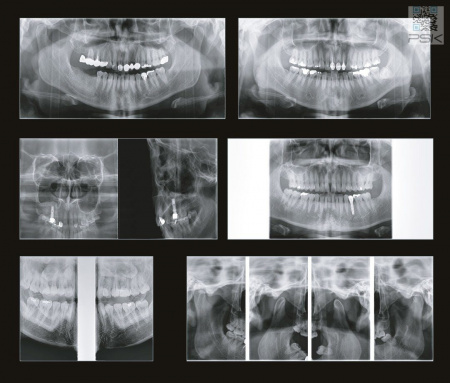

70 мкм в Эндодонтическом режиме 3,5×4 см

Высокотехнологичный детектор с самым высоким разрешением в классе – 70 мкм. Позволяет различить даже самые мелкие анатомические образования и облегчит постановку диагноза в сложных случаях. А вместе с применением алгоритма SMARF инородные тела из металла не испортят качество снимков.

Алгоритм уменьшения вторичного излучения от металлов

Умная Функция Уменьшения Артефактов от Металла (Smart Metal Artifact Reduction Function) – позволяет минимизировать артефакты от вторичного излучения металлов и получить необходимую диагностическую информацию для постановки корректного диагноза, а также планирования и контроля проведенного лечения.